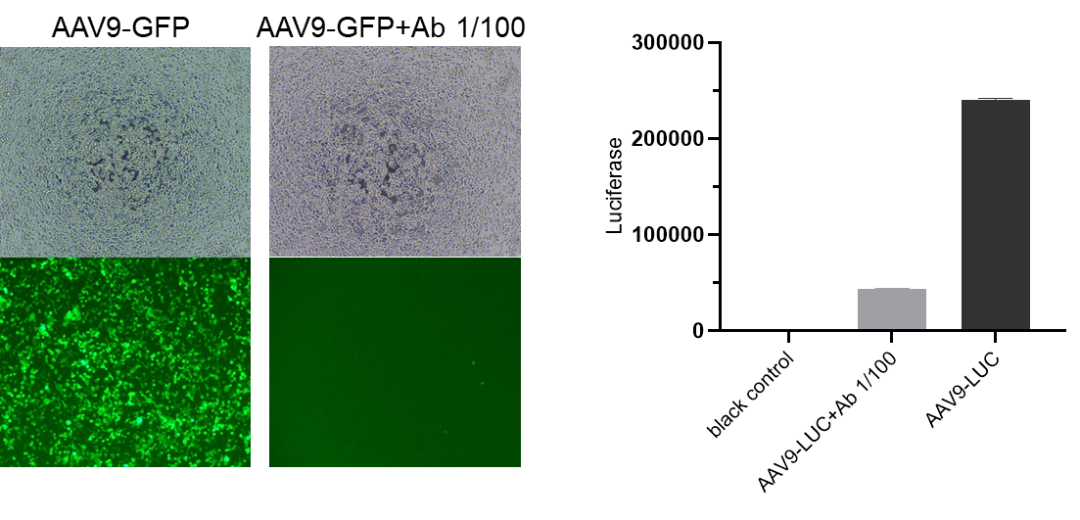

AAV病毒含有病毒的中和抗原,且具有感染细胞活力;中和抗体可以识别AAV病毒,并发生中和反应,降低AAV病毒感染能力,导致携带的报告基因(如绿色荧光蛋白EGFP、荧光素酶Luciferase等)表达量减弱。通过Elispot读数仪扫描计数每孔的荧光斑点数,或多功能酶标仪读取每孔的荧光素酶表达量,将待测样品孔的数值与病毒对照组的数值进行比较,可计算待测样品的抑制百分比。计算当50%病毒被抑制时抗体的稀释倍数的倒数即中和抗体滴度。

感染活性检测示例图